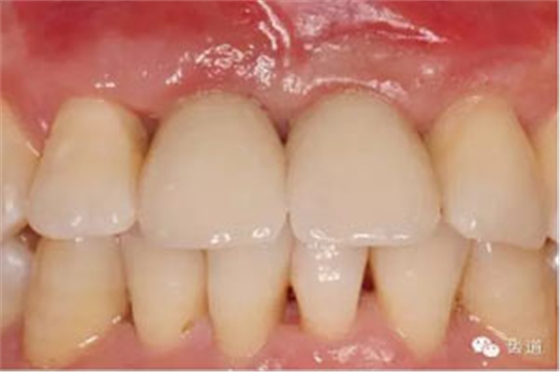

臨時(shí)冠塑形

合面觀

袖口形態(tài)